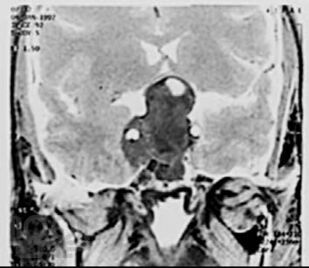

Кратко изложены этиология, особенности эпидемиологии, патогенеза, классификация и основные клинические проявления первичных опухолей головного мозга, современные принципы клиники, диагностики и оказания госпитальной помощи больным с данной патологией. Представлены алгоритмы обследования и лечения больных с наиболее часто встречающимися опухолями в зависимости от стадии течения патологического процесса.